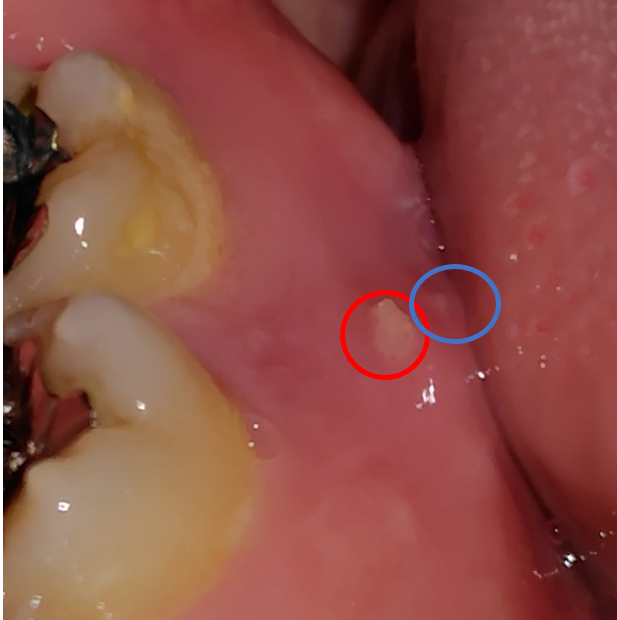

腱鞘炎による右腕の痛みに加え、人差し指も動かせなくなり、約2か月後には人差し指にうっ血が見られるようになりました。

うっ血がひどくなり、症状の悪化が続いてしまったため、6か月後にはある医師からは、「これ以上悪化したら、責任を持って切除しましょう」と親切心からおっしゃいました。